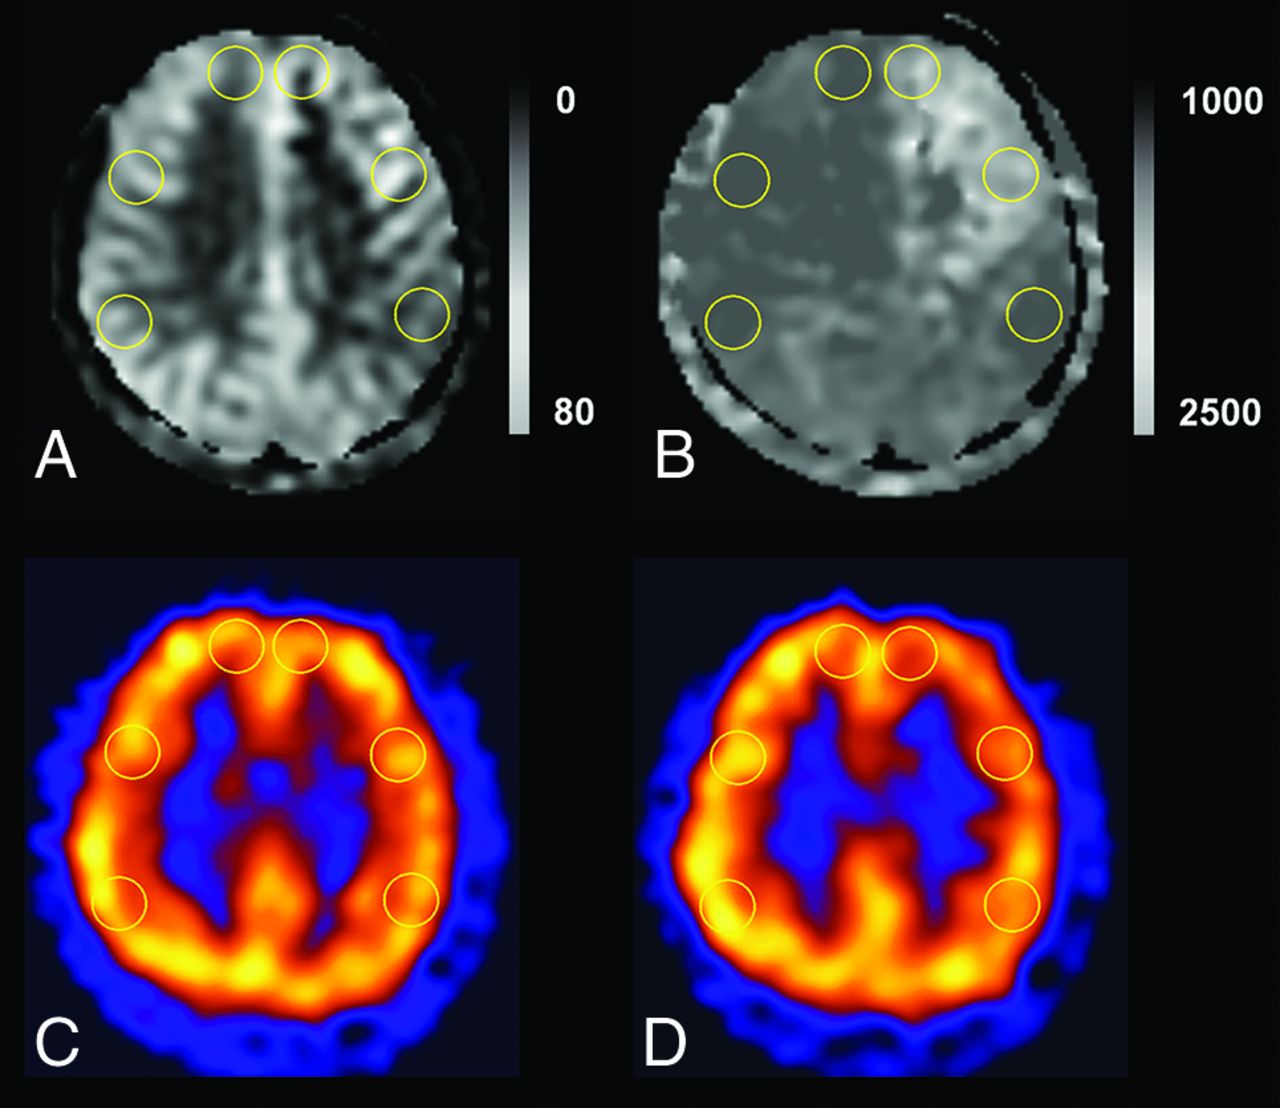

On ASL MR imaging, ROIs were drawn in the gray matter of the major territories of the intracranial arteries and the equivalent site on the contralateral normal side on the ATT and transit time–corrected CBF (TCF) maps directly in the workstation (Fig 1). The ROIs were placed in 6 locations (2 bilateral anterior cerebral artery territories and 4 bilateral MCA territories) on the supraventricular level over a fixed territory in all patients to avoid the infarcted area. ATT [ms] and TCF [mL/100 g/min] were obtained in each territory. The percentage change of TCF is calculated as 100 × [(TCFcontralateral normal − TCFipsilateral affected)/TCFcontralateral normal], and the percentage change of ATT is calculated as 100 × [(ATTcontralateral normal − ATTipsilateral affected)/ATTcontralateral normal].

ROI placements in supraventricular levels on ASL and SPECT. We drew the ROIs in the bilateral anterior cerebral artery territories and anterior and posterior MCA territories in TCF (A), ATT (B), baseline SPECT (C), and acetazolamide challenge SPECT (D). We also drew an ROI in the ipsilateral cerebellum with the highest uptake on visual assessment for normalization of SPECT values.